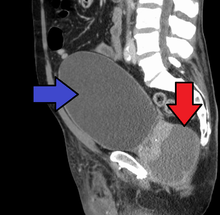

Antibiotics are the first line of treatment in acute prostatitis (Cat. I). Antibiotics usually resolve acute prostatitis infections in a very short time, however a minimum of two to four weeks of therapy is recommended to eradicate the offending organism completely.[4] Appropriate antibiotics should be used, based on the microbe causing the infection. Some antibiotics have very poor penetration of the prostatic capsule, others, such as Ciprofloxacin, Co-trimoxazole and tetracyclines such as doxycycline penetrate well. In acute prostatitis, penetration of the prostate is not as important as for category II because the intense inflammation disrupts the prostate-blood barrier. It is more important to choose a bacteriocidal antibiotic (kills bacteria, e.g. quinolone) rather than a bacteriostatic antibiotic (slows bacterial growth, e.g. tetracycline) for acute potentially life-threatening infections.[5] Severely ill patients may need hospitalization, while nontoxic patients can be treated at home with bed rest, analgesics, stool softeners, and hydration. Patients in urinary retention are best managed with a suprapubic catheter or intermittent catheterization. Lack of clinical response to antibiotics should raise the suspicion of an abscess and prompt an imaging study such as a transrectal ultrasound (TRUS).[6]